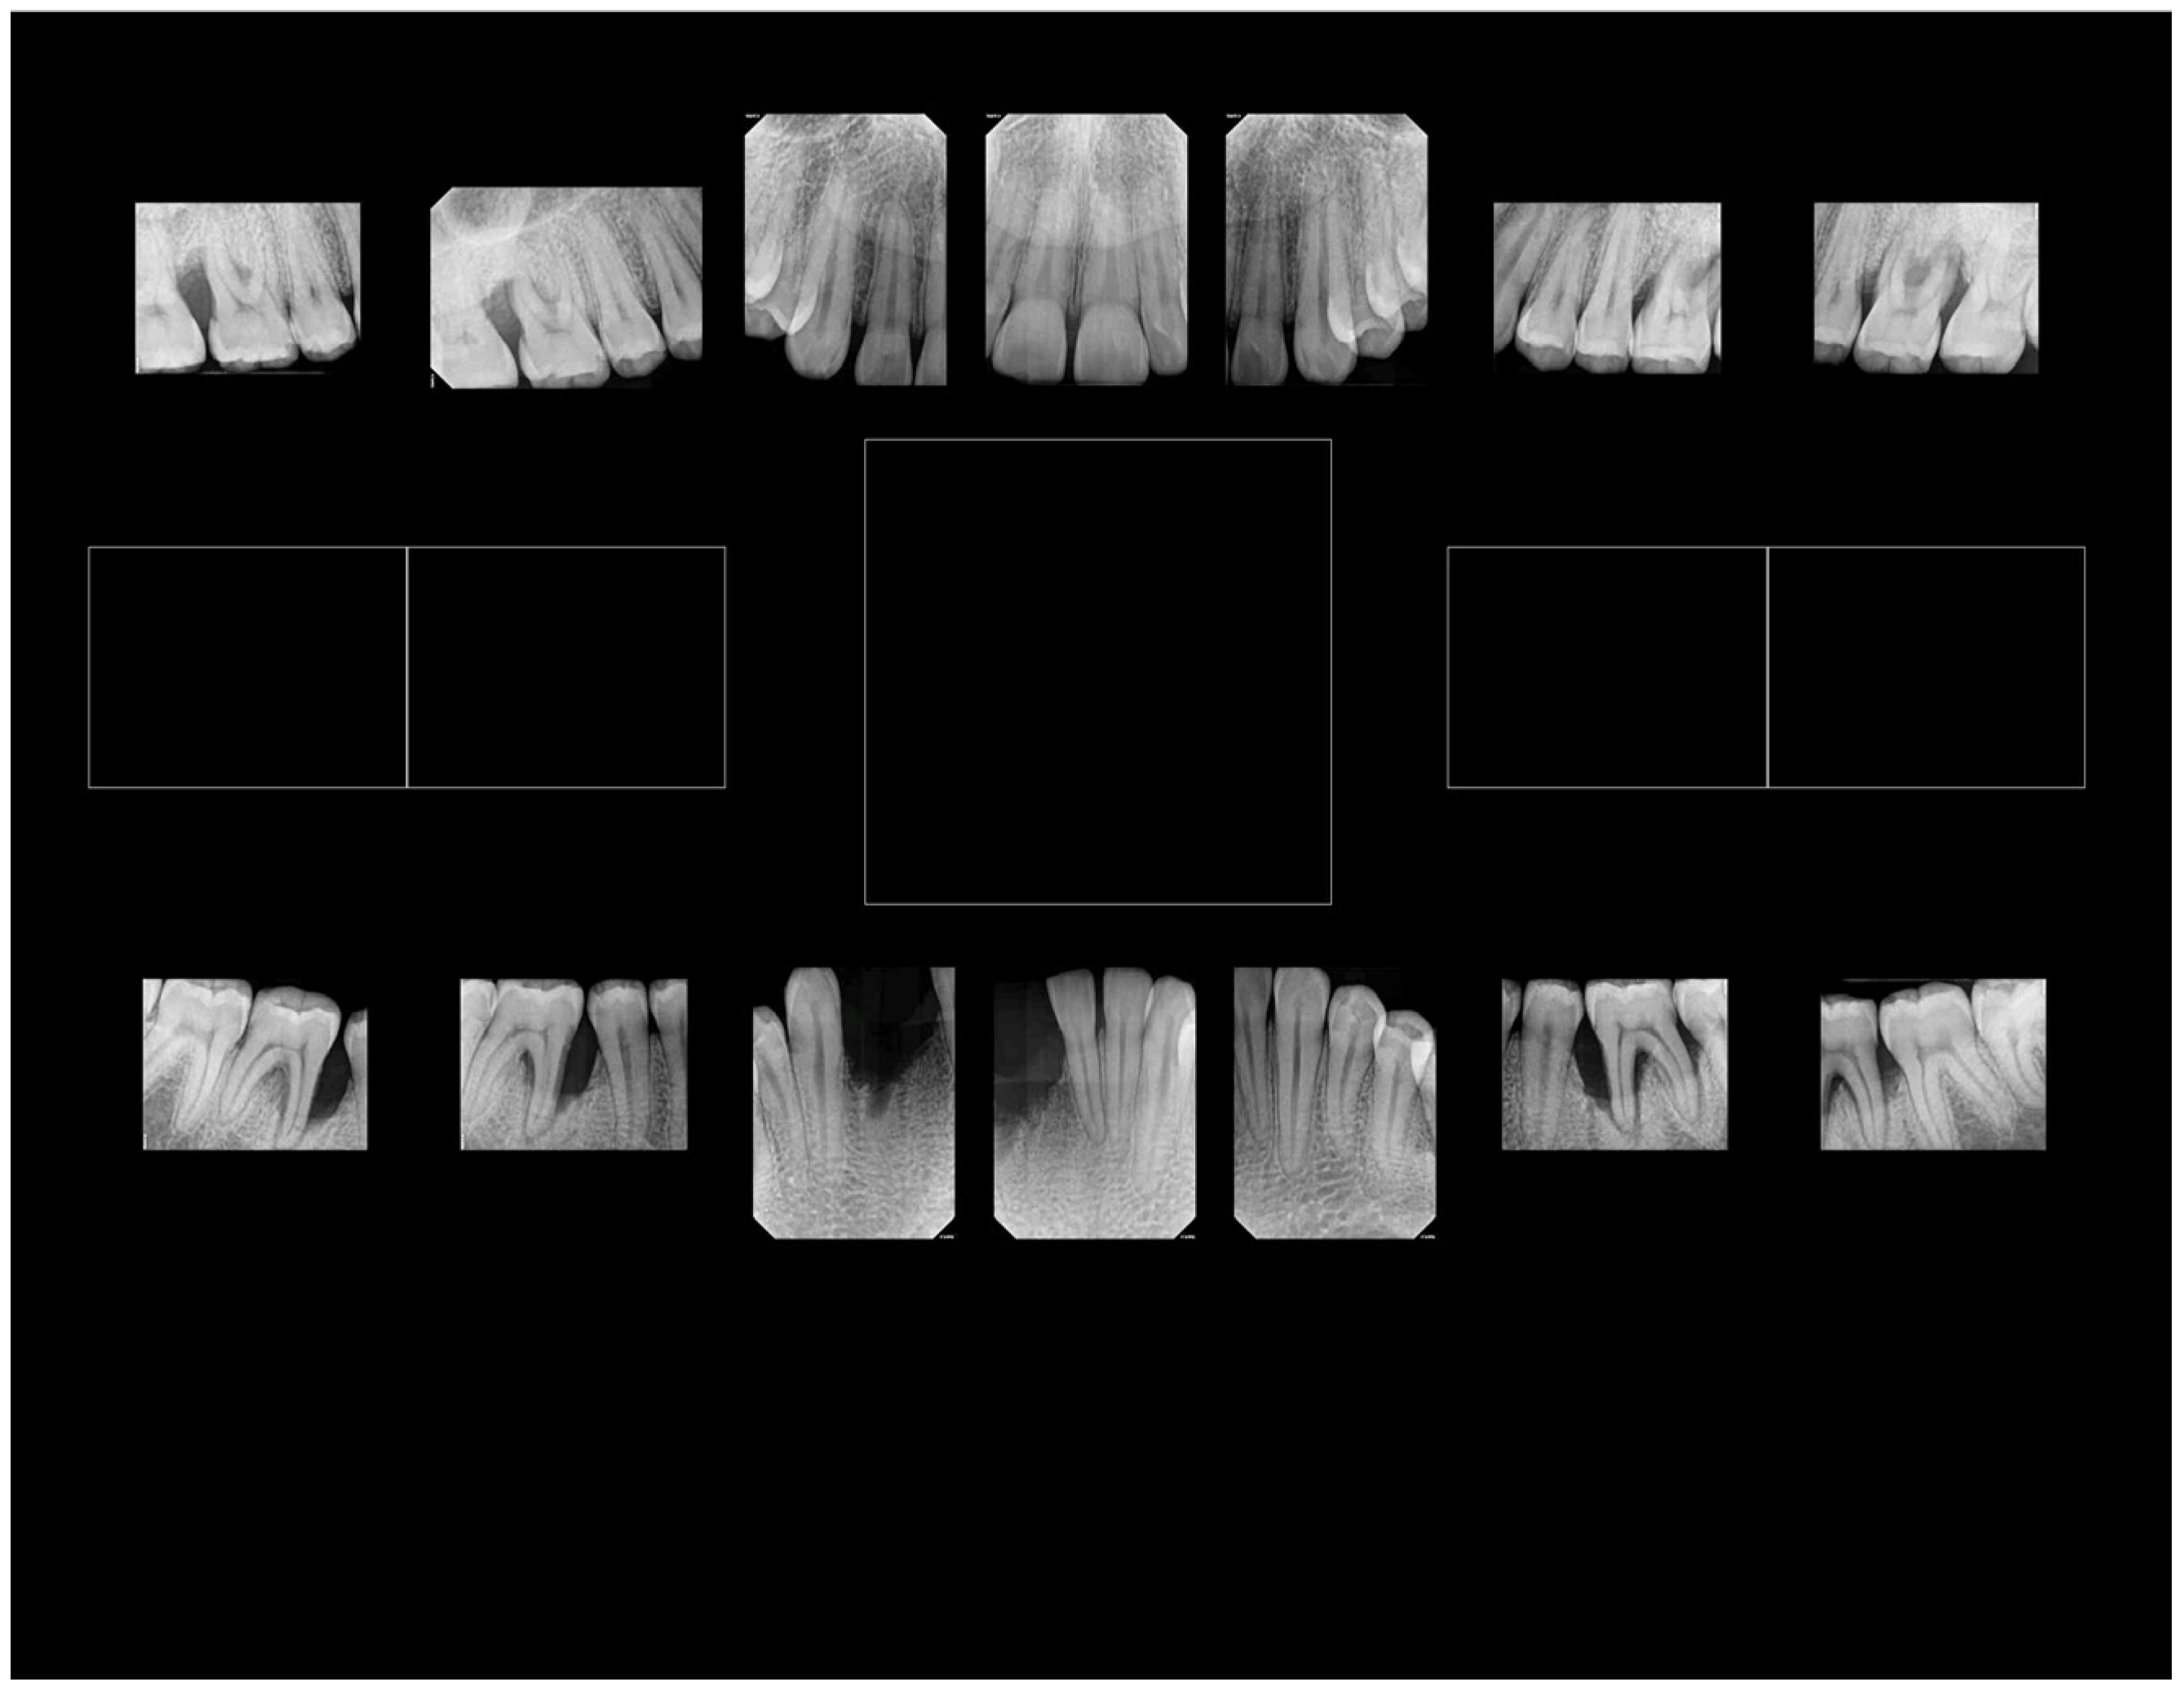

This case is presented to illustrate the distinctive nature of aggressive periodontal bone loss in a 20-year-old patient who reported to our clinic (RSDM) with extensive periodontal disease. After obtaining consent (IRB:PRO#012008035; year = 2009), we collected subgingival plaque, saliva, and buccal cells for analysis. The subgingival sample taken from various healthy and diseased sites had the “b” serotype of Aa with the JP2 promoter region. The patient had only one strain of Aa in his subgingival microbiome isolated from both healthy and diseased sites, with substantially more Aa isolated from diseased sites. We tested the Aa isolates for antibiotic sensitivity and for the presence of the hbpA-1, hpbA-2, and tbp-A pseudogenes using primers reported by Haubek et al. [153]. Saliva was assessed for salivary anti-S. mutans activity and buccal cells were used for the detection of the lactoferrin (LF) single nucleotide polymorphism associated with anti-S. mutans activity [154]. Our primary goal was to use our laboratory data to provide information about Aa antibiotic sensitivity, which could act as a supplement to treatment aimed at resolving this progressive disease in this young patient. The focus on Aa was pragmatic because our previous data had suggested that Aa was necessary but subsequently proved to be insufficient on its own to cause disease [29]; conversely, assessment of the complete consortia was impractical at that time. However, several of our other laboratory assessments proved useful.

While we recovered Aa from the diseased site, we cannot attribute disease to the presence of Aa. Microbial causation can only be implied if the bacterium preceded disease at the site of disease initiation [41]. Therefore, in this case, linking Aa to disease initiation and development can only be seen as speculative. Second, based on the complex patient history, it is reasonable to conclude that confounding social, psychological, and ecological modifiers could have contributed to a diminished host response, factors that could clearly be implicated in disease progression [42]. Based on antibiotic sensitivity testing, we ruled out the use of penicillin derivatives due to Aa insensitivity, which was a clinically useful finding. Furthermore, the age of the patient, the tooth loss attributed to periodontal disease, and the extent of bone loss indicated an aggressive nature of localized disease in this patient (Figure 4). We posit, based on tooth location and the patient’s history, that the loss of two mandibular incisors was due to extensive periodontal disease (Figure 4). This conclusion appears to be a realistic appraisal of tooth loss as a consequence of (1) the dramatic level of bone loss in the existing molars and (2) the complete lack of caries in this subject’s mouth (and the fact that the mandibular incisors lost are not typically vulnerable to caries) [155]. Testing for salivary anti-S. mutans activity gave an incomplete picture since several other oral microorganisms can also be related to caries [156]. The fact that anti-LF antibodies had no effect on S. mutans suggests that factors other than LF were responsible for the anti-S. mutans activity. This finding agrees with our previous data, where 20–30% of subjects tested showed factors independent of LF that also killed S. mutans [154]. The level of bone loss and lack of proximal decay reflects a pattern seen in many cases of LAgP [157,158]. Finally, point mutations in the hpbA-1 and tnp-B pseudogenes suggested that the patient was of West African descent [153].

In summary, the clinical presentation, coupled with the presence of minimal plaque, the absence of proximal decay, severe periodontal disease, and the presence of Aa, all present a strong argument that LAgP is a disease uniquely distinguishable from periodontitis that occurs in adults (Figure 5).